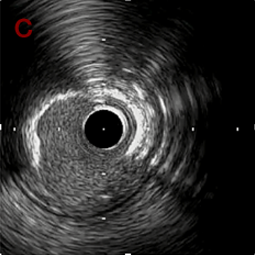

IVUS imaging

IVUSでは8時方向からPD枝がはいいてくる。

PreのIVUSではaの部位のみlipid plaqueを認め削ることでdistal embolismのリスクがあり、そのほかは270度の偏心性石灰化であるがwire biasは良好。